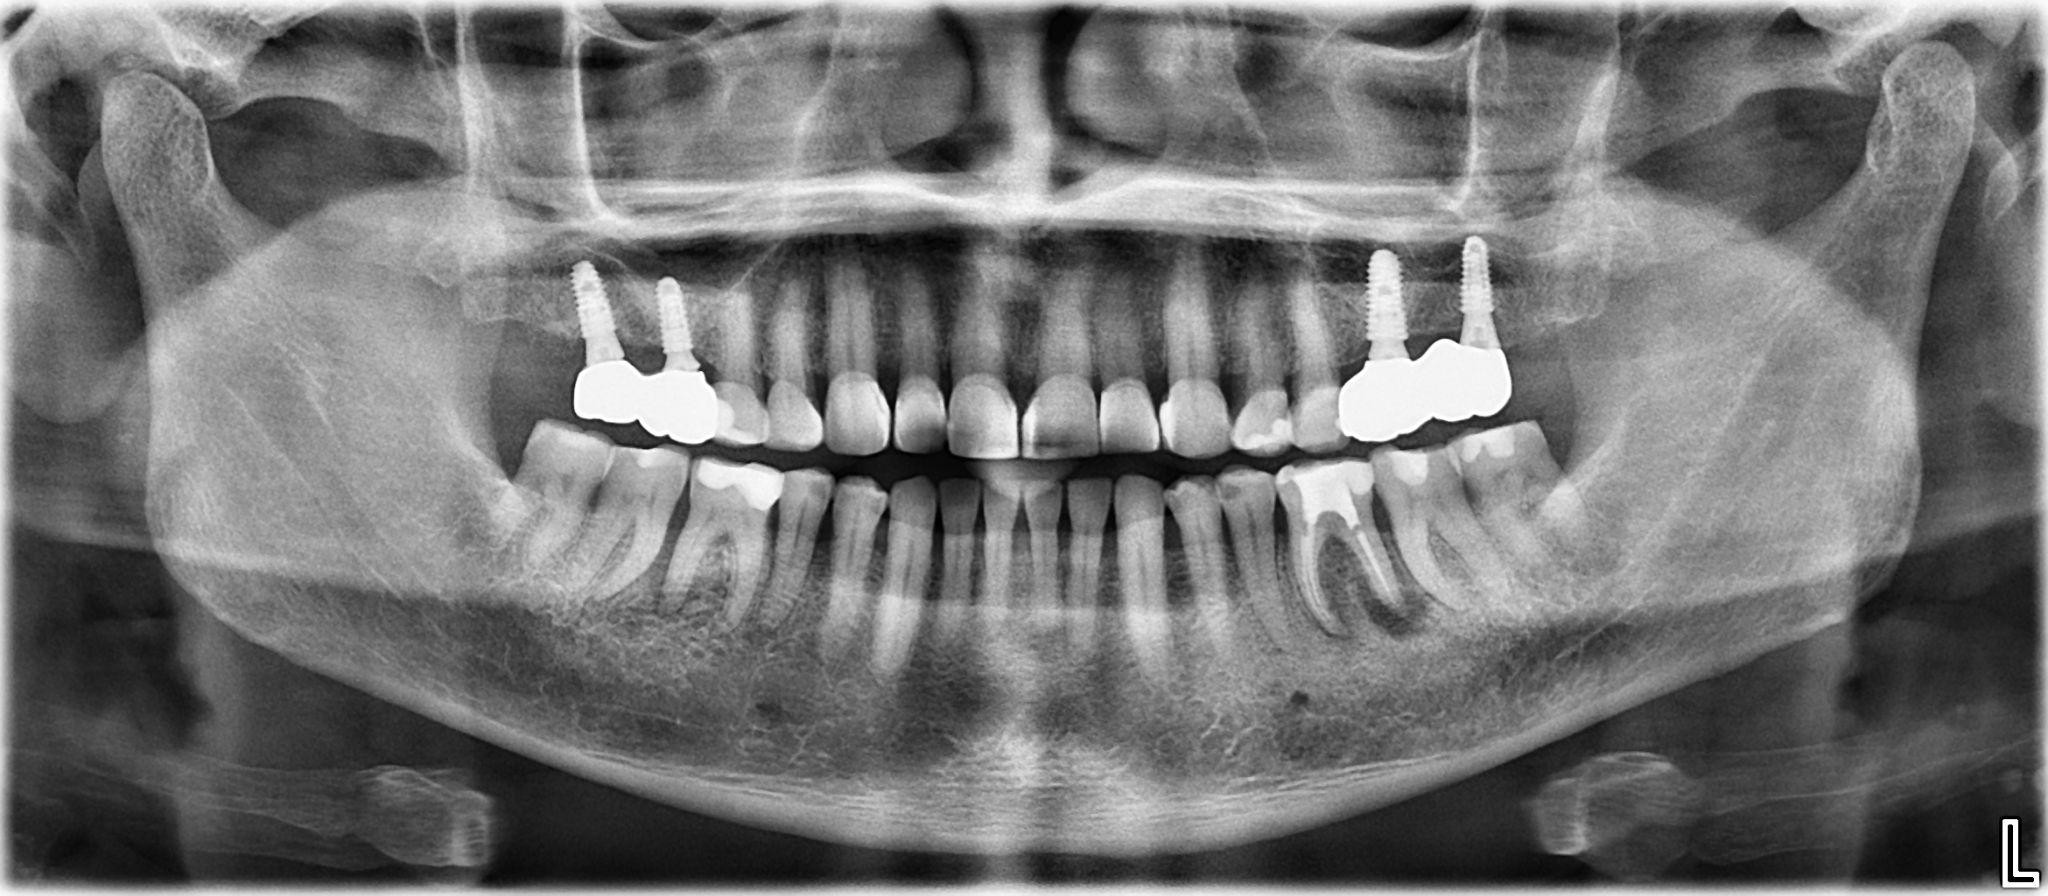

8. What option cannot be selected for the upper jaw of this panoramic X ray?

9 / 25

9. What option cannot be selected for the lower jaw of this panoramic X ray?

10 / 25

10. What option cannot be selected for the first quadrant of this panoramic X ray?

11 / 25

11. What option cannot be selected for the second quadrant of this panoramic X ray?

12 / 25

12. What option cannot be selected for the third quadrant of this panoramic X ray?

13 / 25

13. What option cannot be selected for the forth quadrant of this panoramic X ray?